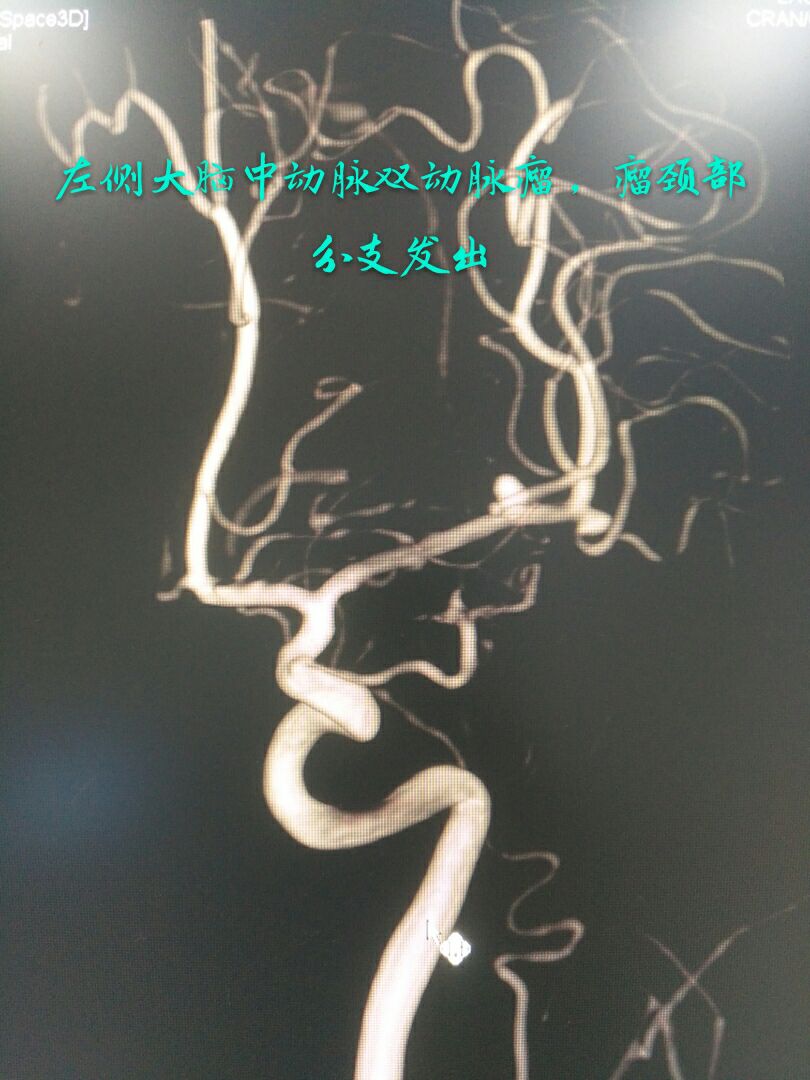

病例五:中年女性患者,2年前因脑梗塞导致一侧肢体不完全性瘫痪,近一年间断性头痛,DSA示左侧大脑中动脉双胞胎动脉瘤,载瘤动脉纤细,瘤颈部累及重要分支

难点:载瘤动脉保护容易,但瘤颈部分支纤细,无法释放支架,保护困难,最终采用单支架半释放、推灯笼技术栓塞远端动脉瘤,全释放并推灯笼技术栓塞近段动脉瘤,瘤颈部分支得到充分保护